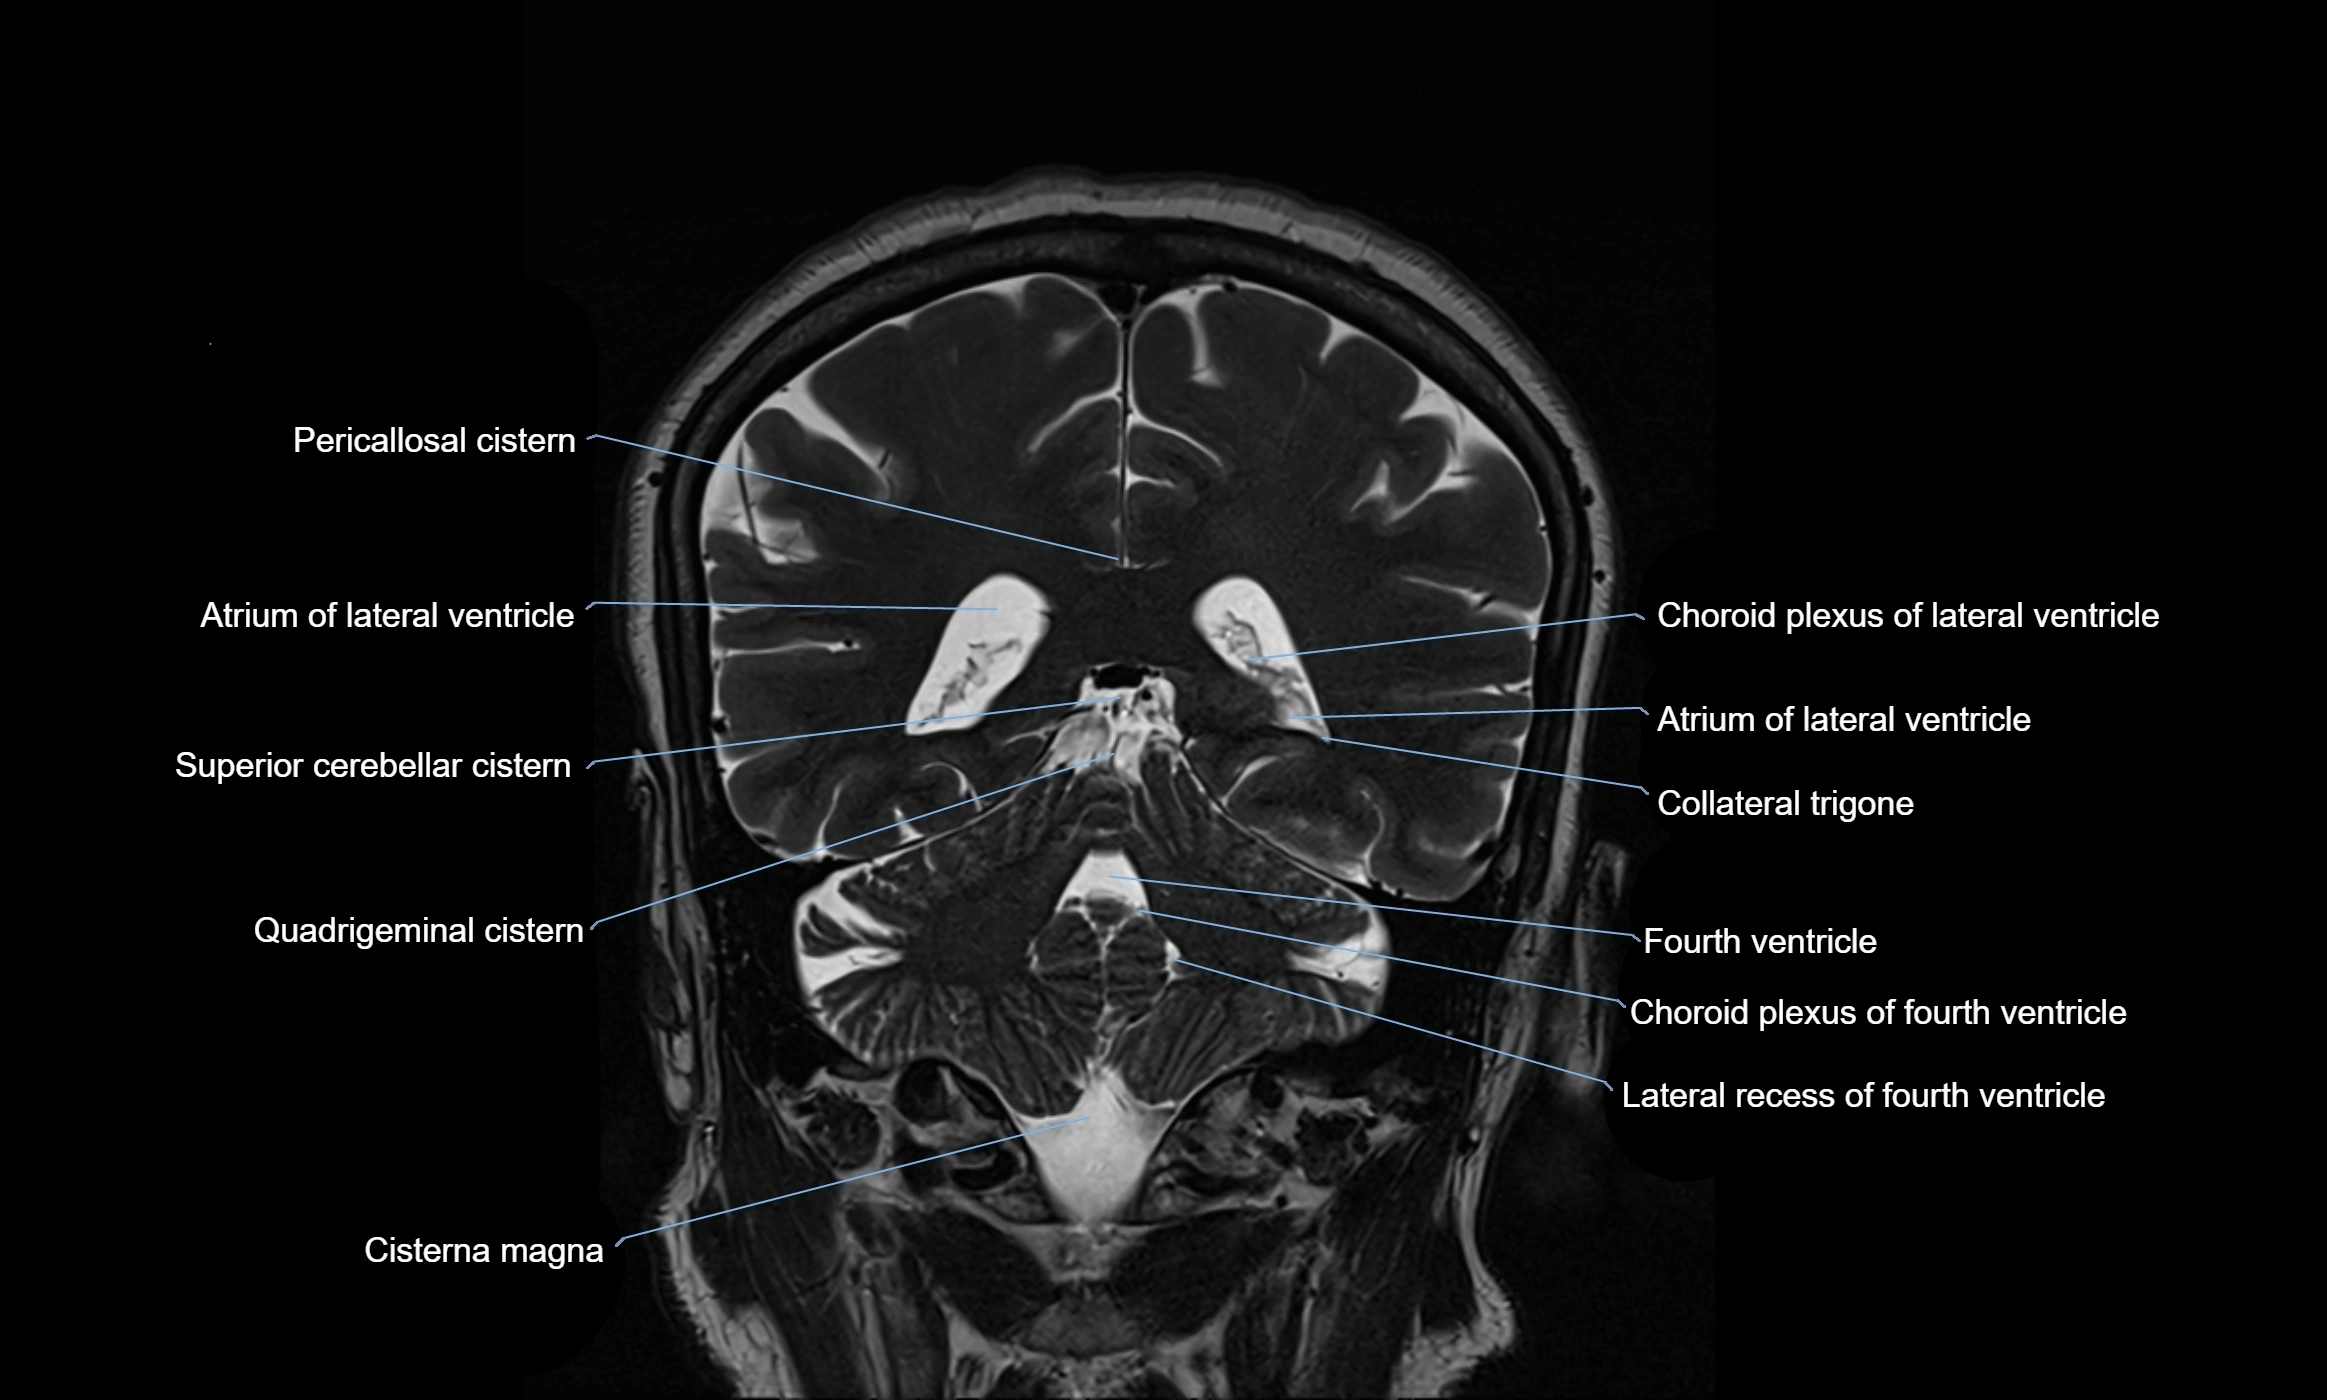

CT image

image